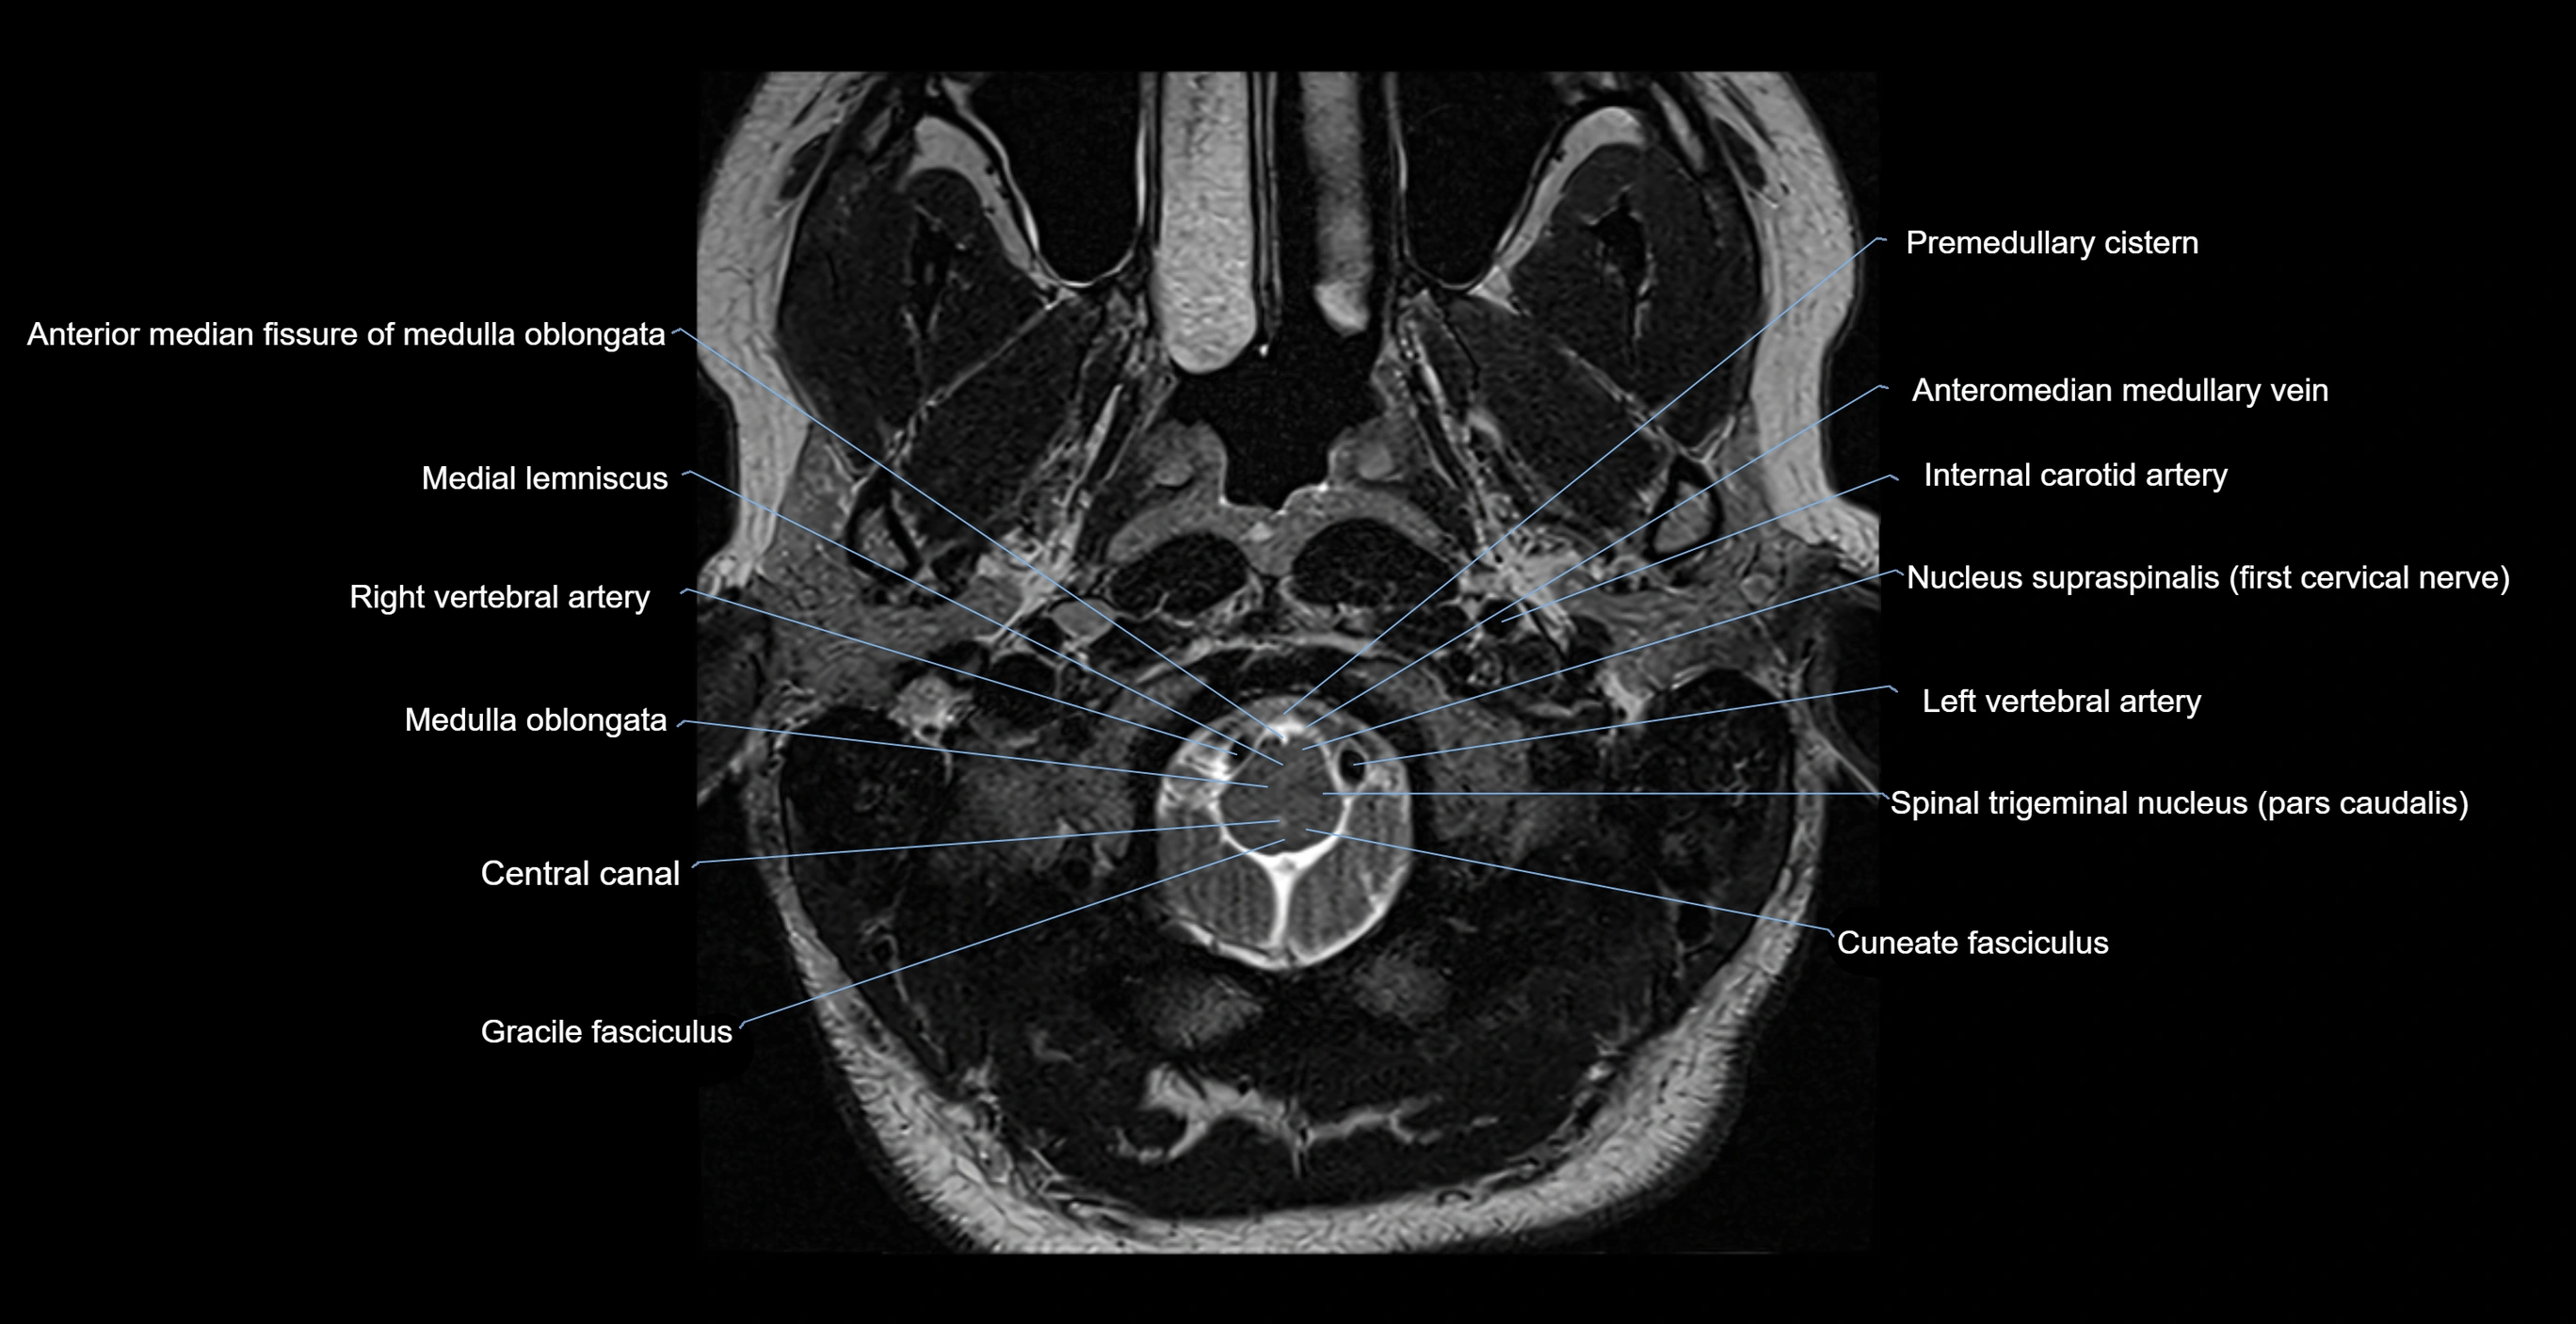

MRI images